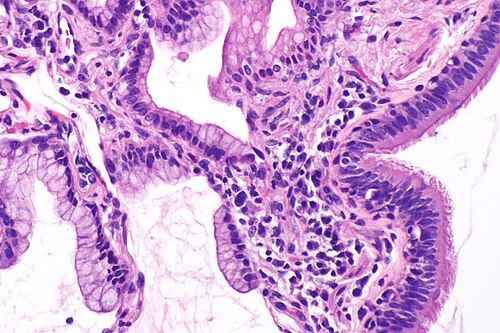

Some forms of cancer have no or minimal nuclear pleomorphism; mucinous adenocarcinoma of the lung (left of image) looks similar to (benign) gastric foveolar epithelium and in this image is juxtaposed with benign ciliated epithelium (right of image). H&E stain.

Nuclear pleomorphism is a common finding in malignant lesions. Anisonucleosis is often used as a synonym for nuclear pleomorphism; iso- means equal or identical,[1] and an- means not.[2]

Nuclear pleomorphism is the marked variation of:[3]

- Nuclear size.

- Nuclear shape.

- Nuclear staining (especially with hyperchromasia).

Memory device 3 S: size, shape, staining.